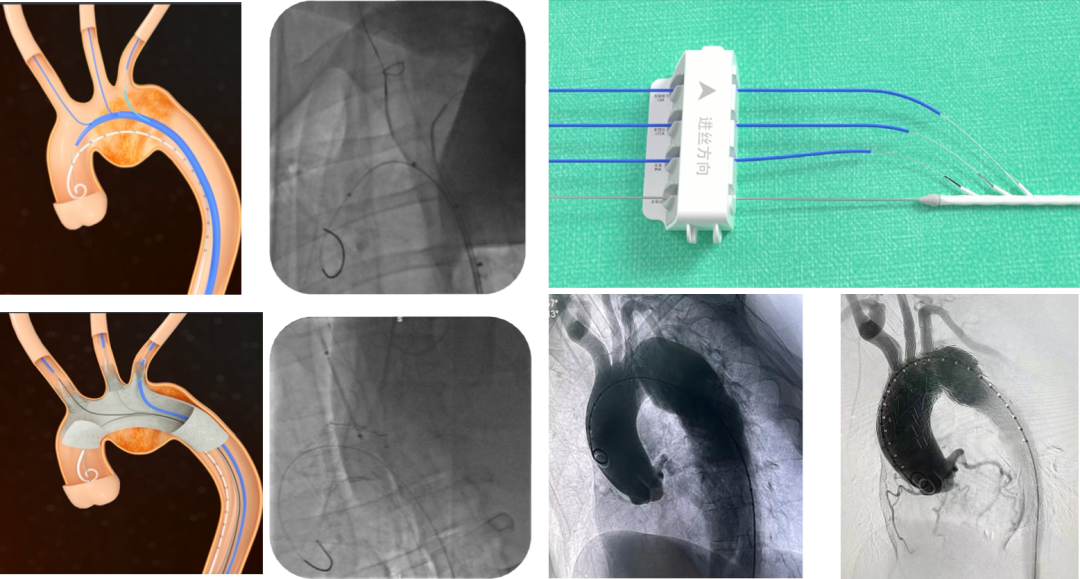

【体外预三开窗】精准规划的选择

体外预开窗技术是根据术前测量结果,在支架上预留对应分支开口,支架释放后开口对准分支开口以保留分支血供。

技术改进:通过3D打印模型辅助术中操作,先对准左颈总动脉,再对准左锁骨下动脉,用球囊扩张固定后再释放支架,为纠错和防止移位争取时间。

复杂病例应用:巨大弓部动脉瘤(5.5cm)且左锁骨下动脉位于瘤腔内:在预开窗基础上加做左锁骨下动脉内嵌分支,配合3D打印模型辅助和束径技术,术后随访效果理想

A型夹层合并迷走左椎动脉:针对头臂干、左颈总和左锁骨下动脉进行预开窗,对非优势且纤细的迷走左椎动脉仅作小洞处理,术中对位良好

【分支支架开窗技术】未来趋势的探索

分支支架是指自带弓上分支的主动脉覆膜支架,尤其是三分支支架的使用促进了全腔内修复术的重大进展。

Castor支架是目前国内唯一上市的分支支架产品,研究表明术后长达92个月随访,并发症发生率为0.035%。可结合左锁骨下动脉开窗技术,也可重建左颈总动脉血运,适用于Z2和Z3区病变。